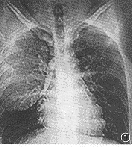

图2 右侧胸腔内类扇形肿物,外缘紧贴侧后胸壁,内见点状钙化

CT示右侧胸腔内巨大扇形肿块,内见点、线状钙化,其余为均匀一致脂肪密度,CT值-68HU(图2)。邻近肺组织受压,局部肺纹理密集。CT诊断:胸腔脂肪瘤。

手术病理证实:胸腔脂肪瘤。

讨论 胸腔如此巨大脂肪瘤较少见,仅凭X线平片难与肺包虫及其他良性肿瘤鉴别,而CT扫描则能明确诊断。